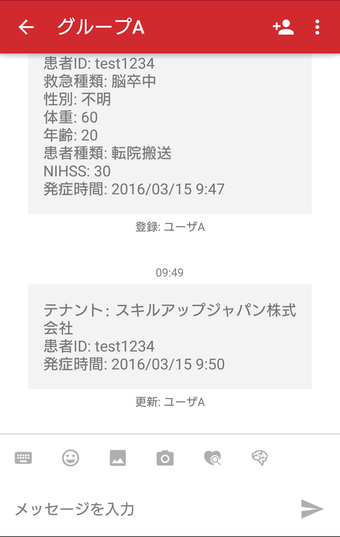

Untuk memberikan perawatan terbaik bagi pasien, para profesional kesehatan perlu memiliki akses cepat dan mudah ke riwayat medis pasien, termasuk data laboratorium, resep obat, dan laporan radiologi. Dengan Join, mereka dapat dengan mudah mengirimkan gambar rekam medis pasien kepada rekan mereka, sehingga mereka dapat dengan cepat dan efisien membuat diagnosis dan rencana perawatan.

Join juga memungkinkan mereka untuk berkomunikasi dengan rekan mereka tentang kondisi pasien, yang sangat penting untuk memberikan perawatan terbaik.